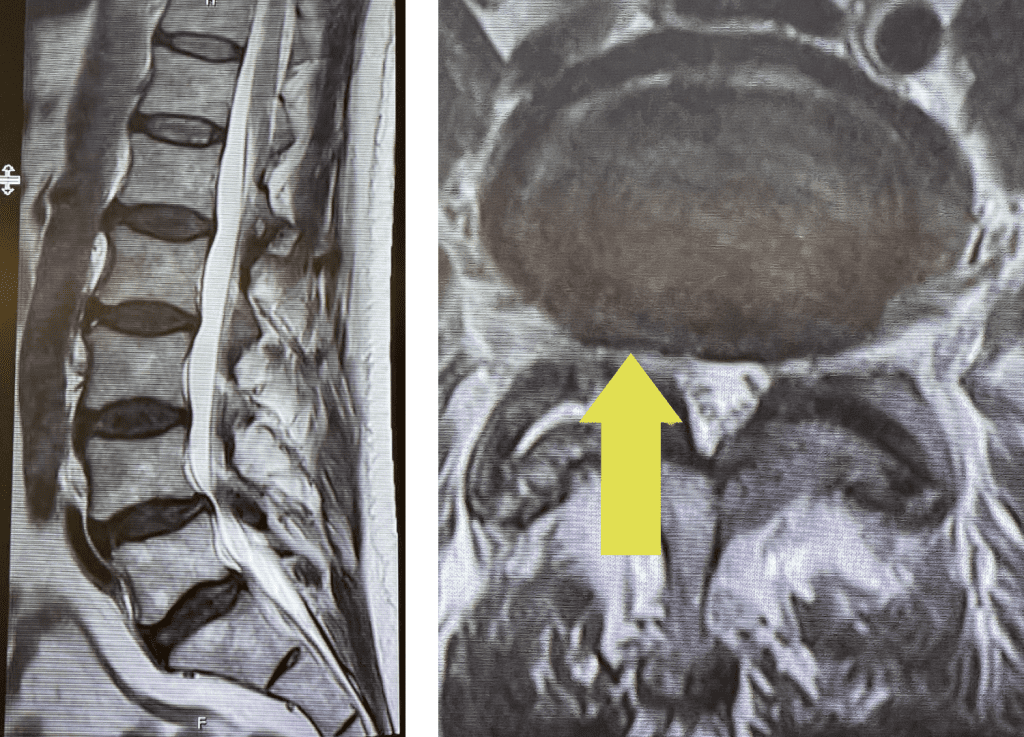

Fig 3: Intraoperative lumbar fluoroscopic lateral and AP images demonstrating good screw placement in performing an L4-5 fusion.

During the surgery we encountered the “cyst” as it was coming from inside or medial joint space between the two bony processes that make up the facet joint itself, like two puzzle pieces that fit together with a synovial-lined space that can for a degenerative synovial cyst. The cyst is like a pimple and actually is quite satisfying to pop and release the material that looks like curd as it is rarely liquid. Because of the consistency and the location, they are not really able to be aspirated or found. After we did what we set out to do which was to make the nerve sac without any pressure as well as the L5 nerve roots, which are most affected at this level. We performed a fusion with two titanium screws in L4 and two in L5, which were connected by rods that were bent or lordosed (Fig 3). They are easy to put in and serve the purpose of connecting the two levels to prevent any relative motion or translation of L4 on L5. This also most importantly prevents the body from signaling the spine to make arthritis to attempt to auto stabilize itself. After the surgery the patient had relief of his right leg pain and had an uneventful postoperative course.